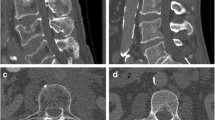

To derive BMD measurements from original as well as virtual low-dose and sparse-sampled MDCT scans with FBP or SIR, regions of interest (ROIs) were placed in the femoral neck of the left and right sides of each subject. First, axial images of the dataset with 100% of the tube current and 100% of the projections (D100 P100), using FBP as the clinical standard of reference, were opened using ImageJ (https://imagej.nih.gov/ij/) [31, 32]. Then, we identified the axial slice in which the neck was visualized best and drew a quadrangular ROI in this section, including the cortical and trabecular bone compartments (Fig. 1). The same placement strategy and shape of the ROI have been used in a previous study of our group [9]. The two ROIs (femoral neck of both sides) were saved for each subject, and the individual ROIs in the used image stack (D100 P100 with FBP) were then transferred (as intrinsically co-registered) to the other datasets containing the virtual low-dose (D50 P100, D25 P100, and D10 P100) and sparse-sampled imaging data (D100 P50, D100 P25, and D100 P10) of the respective subject, considering both FBP and SIR. We then extracted mean HU from these ROIs, which were subsequently converted into volumetric BMD values (in g/cm3) using the information of the reference phantom [9, 13]. The BMD values of the left and right sides were averaged in each subject.

Placement of regions of interest (ROIs). This figure illustrates the placement of a ROI in the femoral neck in a representative case using axial slices derived from full-dose multi-detector computed tomography (MDCT) using filtered back projection (FBP). The ROI was quadrangular and included the cortex. ROIs were not placed in areas with circumscribed lucencies (e.g., cystic lesions) or sclerosis (e.g., bone islands). The placement of the ROI at the other side’s femoral neck was conducted in an analogous way